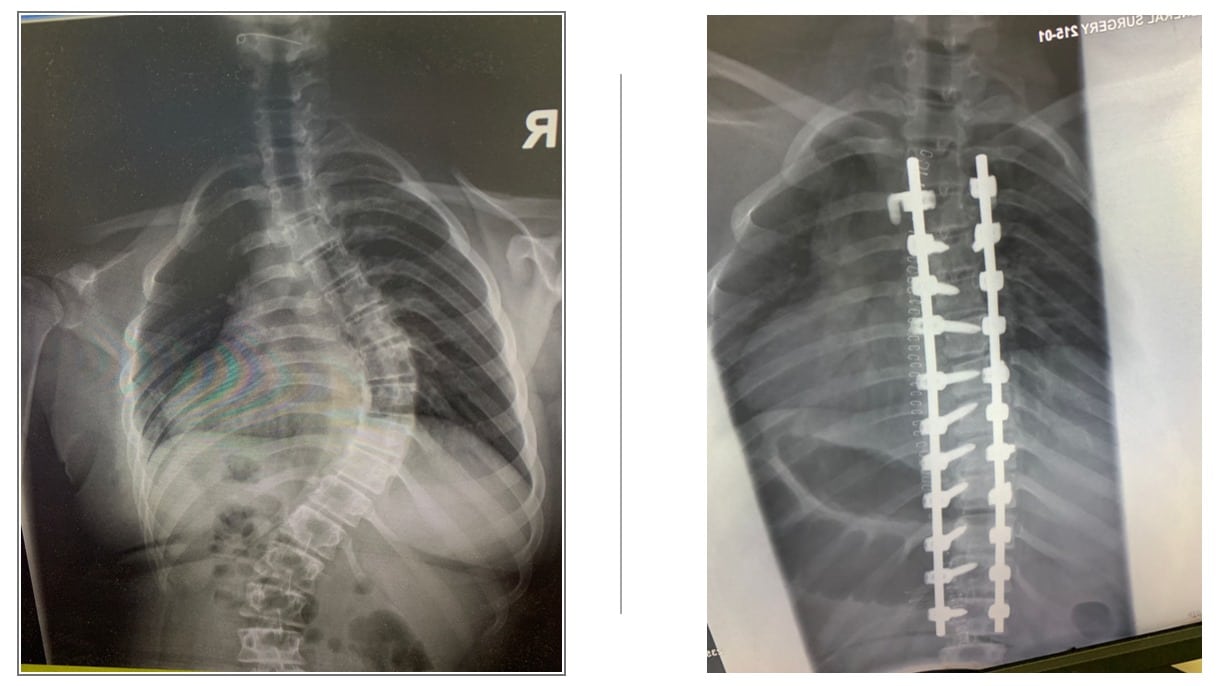

وأظهرت الصور قبل العملية مدى انحناء العمود الفقري، في حين تُبرز الصور بعدها تحولات كبيرة لم تُحسن فقط من صحة المريضة الجسدية بل رفعت من ثقتها بنفسها وجودة حياتها بشكل عام.

أجريت في مستشفى الحسين "السلط الجديد "، عملية تصحيح عمود فقري لأول مرة لمريضة تبلغ من العمر 14 عاماً تعاني من انحناء شديد في العمود الفقري بشكل كبير على حياتها اليومية وصحتها العامة.

وقال مدير المستشفى الدكتور رامي بشير أبو رمان، إنه بفضل كفاءة وخبرة و احترافية الفريق الجراحي، أجريت عملية تصحيح للعمود الفقري وتثبيت ودمج الفقرات بنجاح، مبينا أن هذه العملية تمثل تحدياً تقنياً يتطلب الخبرة والتخصص العالي.